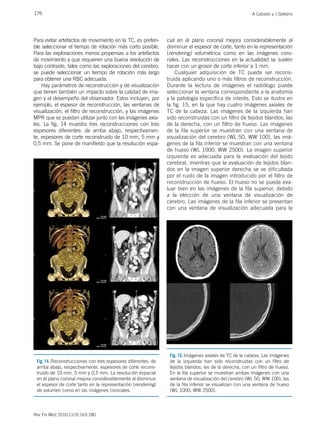

Hay parámetros de reconstrucción y de visualización

les. La fig. 14 muestra tres reconstrucciones con tres

espesores diferentes: de arriba abajo, respectivamen-

te, espesores de corte reconstruido de 10 mm, 5 mm y

0,5 mm. Se pone de manifiesto que la resolución espa-

cial en el plano coronal mejora considerablemente al

disminuir el espesor de corte, tanto en la representación

(rendering) volumétrica como en las imágenes coro-

nales. Las reconstrucciones en la actualidad se suelen

hacer con un grosor de corte inferior a 1 mm.

la fig. 15, en la que hay cuatro imágenes axiales de

TC de la cabeza. Las imágenes de la izquierda han

sido reconstruidas con un filtro de tejidos blandos; las

de la derecha, con un filtro de hueso. Las imágenes

de la fila superior se muestran con una ventana de

visualización del cerebro (WL 50, WW 100), las imá-

genes de la fila inferior se muestran con una ventana

de hueso (WL 1000; WW 2500). La imagen superior

izquierda es adecuada para la evaluación del tejido

cerebral, mientras que la evaluación de tejidos blan-

dos en la imagen superior derecha se ve dificultada

por el ruido de la imagen introducido por el filtro de

reconstrucción de hueso. El hueso no se puede eva-

luar bien en las imágenes de la fila superior, debido

a la elección de una ventana de visualización de

cerebro. Las imágenes de la fila inferior se presentan

con una ventana de visualización adecuada para la

Fig. 15. Imágenes axiales de TC de la cabeza. Las imágenes

de la izquierda han sido reconstruidas con un filtro de

tejidos blandos; las de la derecha, con un filtro de hueso.

En la fila superior se muestran ambas imágenes con una

ventana de visualización del cerebro (WL 50, WW 100), las

de la fila inferior se visualizan con una ventana de hueso

(WL 1000, WW 2500).

Fig. 14. Reconstrucciones con tres espesores diferentes: de

arriba abajo, respectivamente, espesores de corte recons-

truido de 10 mm, 5 mm y 0,5 mm. La resolución espacial

en el plano coronal mejora considerablemente al disminuir

el espesor de corte tanto en la representación (rendering)

de volumen como en las imágenes coronales.

evaluación de los huesos. Los detalles en el cráneo se

aprecian mejor en la imagen inferior derecha debido

al filtro de reconstrucción de hueso, mientras que en

la imagen inferior izquierda la evaluación de hueso se

hace difícil por no haberse reconstruido con el filtro

adecuado. Asimismo, el tejido cerebral no se puede

evaluar bien en las imágenes de la fila inferior, por no

usarse la ventana adecuada. Todas las imágenes de

la fig. 15 fueron reconstruidas con los datos brutos

de una única adquisición de TC.